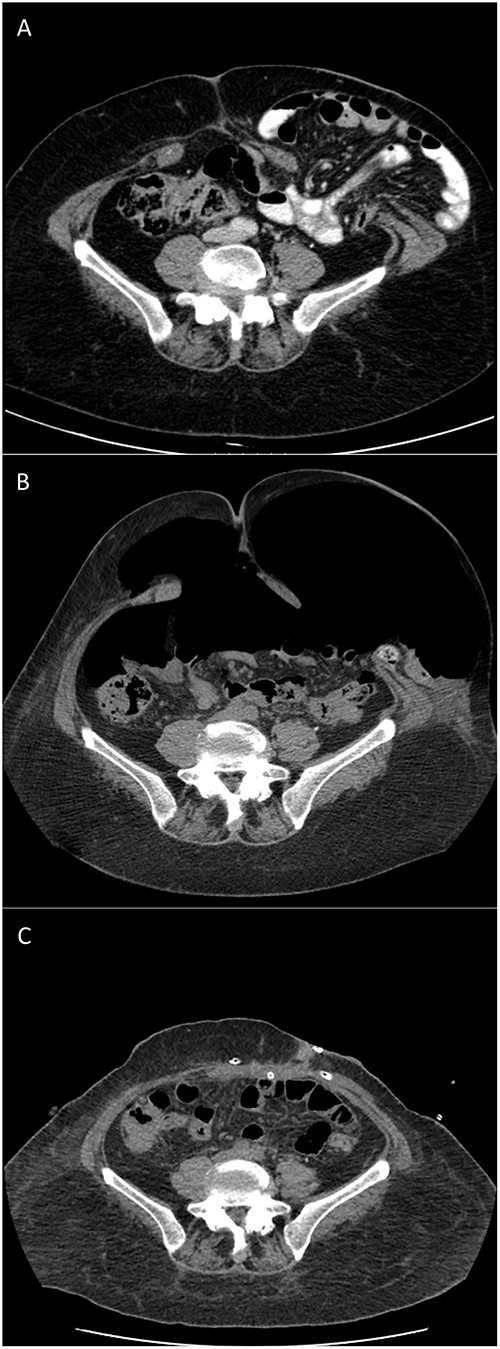

Computed tomography (CT) scan revealed a type IV PH (according to EHS classification [17]) with LOD (Sabbagh = 20%, Tanaka = 0.25), containing small bowel without signs of ischemia or occlusion. Midline incisional hernia had a transversal diameter of 5 cm (Fig. 1A).

CT scans of type IV PH repair after botulinum toxin and PPP: (A) 9 months before surgery; (B) after preoperative BTA and PPP completion; and (C) 3 days postoperative.

BTA was applied 4 weeks before surgery according to our institution’s protocol: 500 U of Dysport® diluted in 20 ml of 0.9% saline distributed over 3 points on each side of the lateral abdominal wall between the costal margin and the iliac crest lateral to the semilunar line. Ten days before surgery the patient was admitted for PPP. An 8 Fr pigtail was inserted by interventional radiology, and a daily insufflation of 1 l of air was performed until a total volume of 7 l was reached (Fig. 1B), limited by the patient’s intolerance for shoulder pain. Rehabilitation program, monitorization of side effects as pain, respiratory and gastrointestinal symptoms, as well as thromboembolism prophylaxis with low molecular weight heparin, compressive socks, and daily mobilization were the main goals of an inpatient procedure. No gastrointestinal complains, including colostomy retraction, were observed during the insufflation. PPP protocol was performed according to that described by Lledó et al. [18].

One day before surgery, a comparative CT scan demonstrated increased abdominal cavity capacitance with bowel content totally reduced (Fig. 1C).